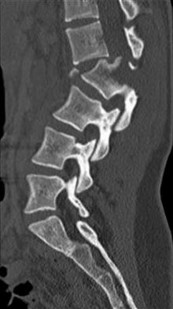

A 35-year-old male construction worker falls 10 feet from scaffolding. He complains of moderate low back pain but has full strength and normal sensation in his lower extremities.

CT imaging shows an L1 burst fracture with 40% loss of anterior vertebral body height and 50% retropulsion into the spinal canal. MRI confirms that the posterior ligamentous complex (PLC) is intact. Based on the Thoracolumbar Injury Classification and Severity (TLICS) score, what is the appropriate score and recommended management?